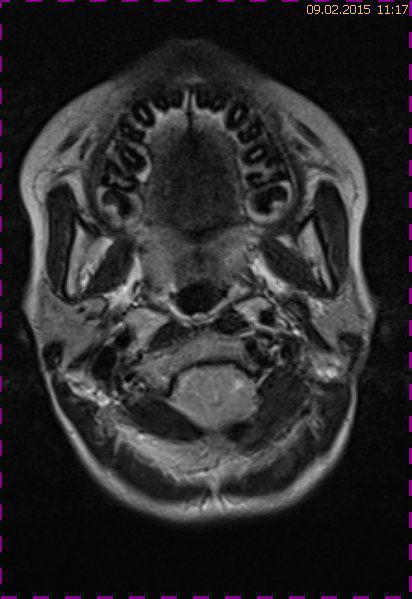

Abb. 3.3 T2 TSE transversal: keine intraventrikuläre Drucksteigerung, keine Zeichen einer Liquordiapedese

Natürlich kann eine Dislokation der Kleinhirntonsillen in das Foramen magnum auch andere Ursachen haben, wie das Fallbeispiel 2 zeigt (Abb. 4.1 bis 4.3). Eine 57-jährige Patientin hatte ein monströses Tentoriummeningeom entwickelt, das zu einer Verlagerung der Kleinhirntonsillen nach kaudal führte. Die postoperativen Verlaufskontrollen zeigten die Repositionierung der Tonsillen in der hinteren Schädelgrube.